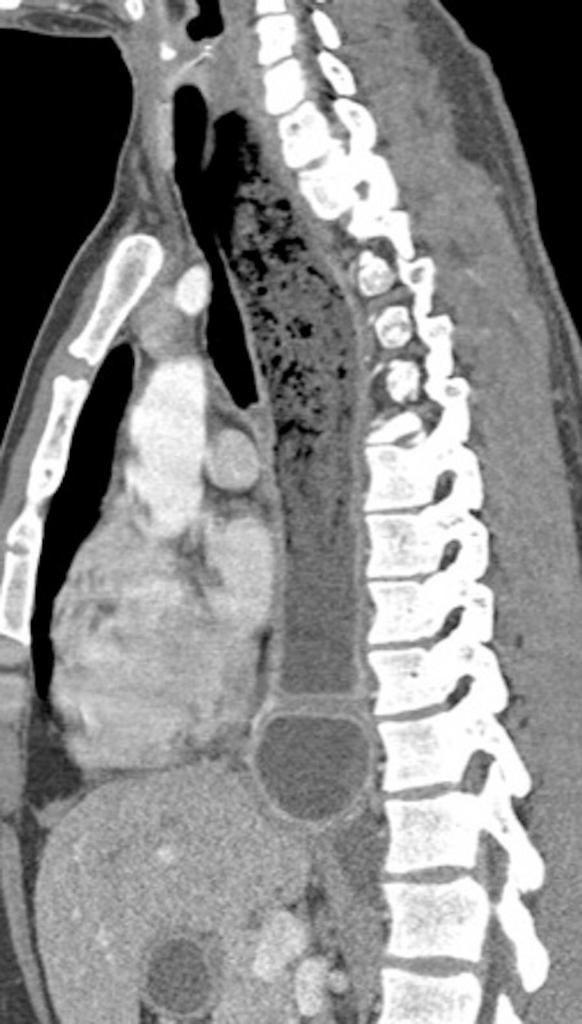

La Acalasia es un trastorno poco frecuente, que dificulta el paso de alimentos y líquidos hacia el estómago. La acalasia se presenta cuando se dañan los nervios del esófago. En consecuencia, el esófago pierde la capacidad de empujar el alimento hacia abajo, y la válvula muscular que se encuentra entre el esófago y el estómago( esfínter esofágico inferior) no se relaja por completo, lo que dificulta que el alimento llegue al estómago.